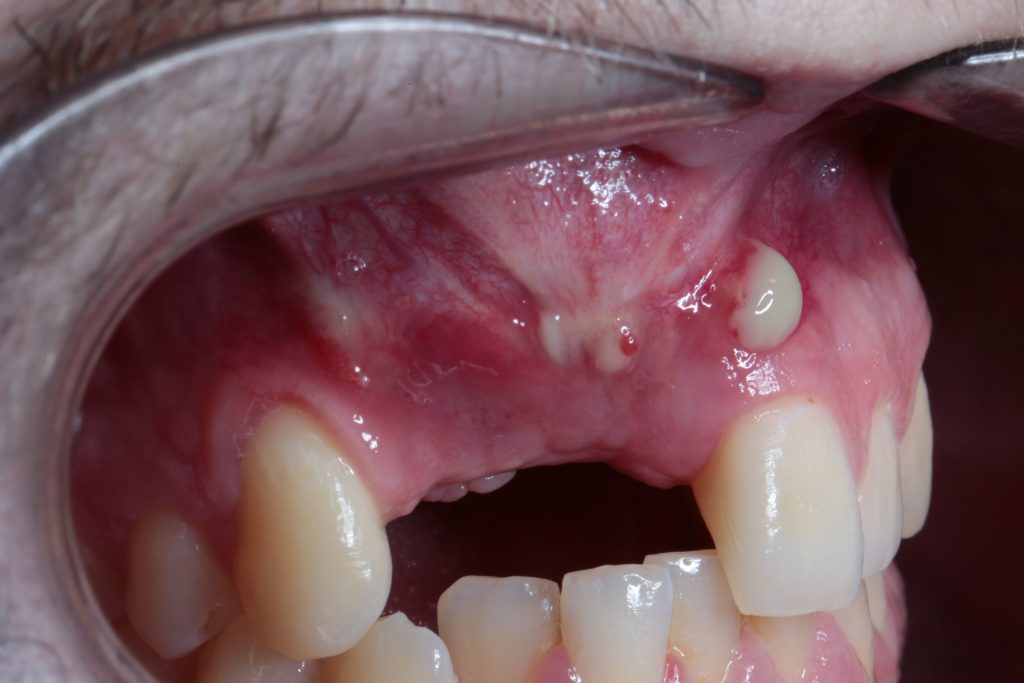

- Canine Management in Oral Implantology: Extraction + Implant Placement + Graft